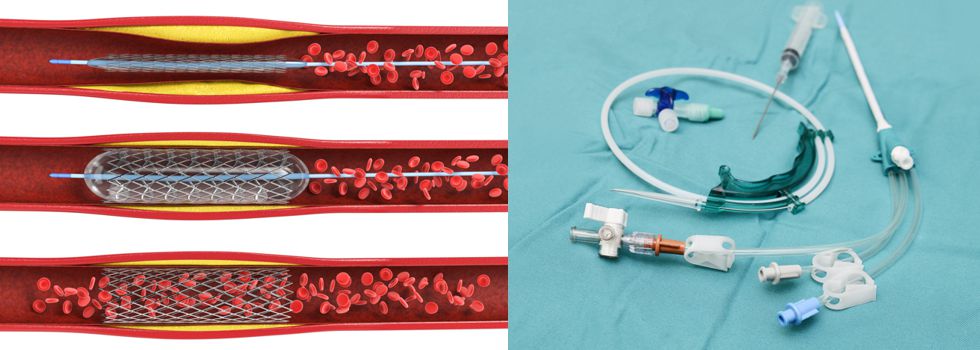

The specialisation track Endoprosthetics focusses on various medical devices and products that permanently remain within the human body and completely or partially assume the functions of the replaced body part. This especially includes knee, shoulder and hip joint endoprostheses respectively.

Graduates are enabled to professionally work in various industrial sectors including but not limited to medical engineering and engineering science. Job definitions may include the development, production and optimisation of medical implants.

Possible fields of application cover complex and comprehensive areas: research, predevelopment, development, precommissioning inspection, calculation, construction, launching as well as dimensioning, evaluation, servicing and maintenance of medical devices for an application within the human body. Besides industrial sectors, capabilities can be found at service providers (TÜV and further governmental and independent testing institutes), public certification and licensing authorities, public research institutions (Max-Planck and Fraunhofer institutes) and universities. Expert activities in a self-employed or regular employment relationship can also be part of the professional perspectives.